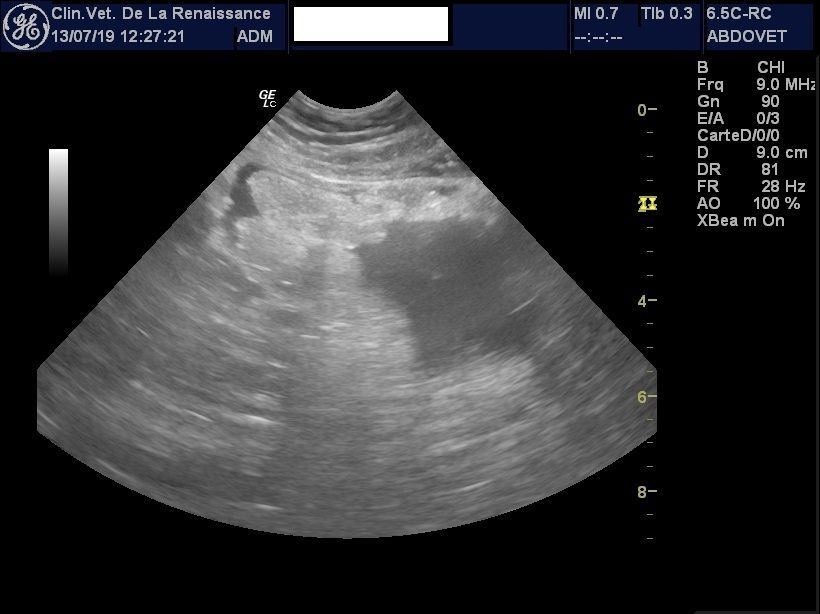

L'échographie

La clinique est équipée d'un échographe pour l'exploration de la cavité abdominale et de ses organes. Nous pouvons réaliser une échographie ciblée sur un organe ou sur l'ensemble des organes abdominaux, dans le cadre d'un diagnostic ou le suivi d'une pathologie ou d'une gestation. Un doppler permet dans le cadre de la gestation de mesurer la fréquence cardiaque des chiots. L'échographie peut être réalisée avec ou sans anesthésie générale en fonction de l'animal.